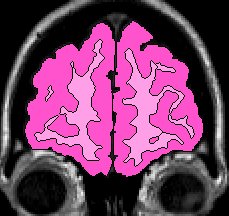

Step One: Beginning at the anterior most tip of the cortex and moving posteriorly, label all cortex as Frontal Lobe (while there is no insula present (Fig 10-11).

Figure 10                      Figure

11

Step Two: When insula is present, but the temporal lobe has not yet connected with the frontal lobe, label all cortex surrounding it as Frontal Lobe. (Fig 12)

Figure 12